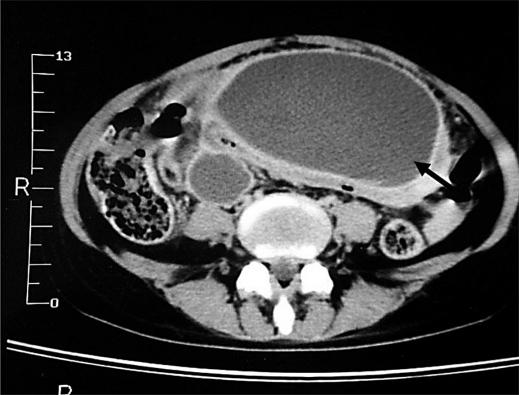

The association between systemic lupus erythematosus (SLE) and chronic pancreatitis (CP) is extremely rare. Up to now, only six cases have been reported. We report the case of a young woman who presented her first episode of abdominal pain and hyperamylasemia at the onset of SLE and developed chronic calcifying pancreatitis after a two year period.

系统性红斑狼疮(SLE)与慢性胰腺炎(CP)之间的关联极为罕见。截至目前,仅报告过6例。我们报告了一名年轻女性的病例,她在系统性红斑狼疮发病时首次出现腹痛和高淀粉酶血症,并在两年后发展为慢性钙化性胰腺炎。